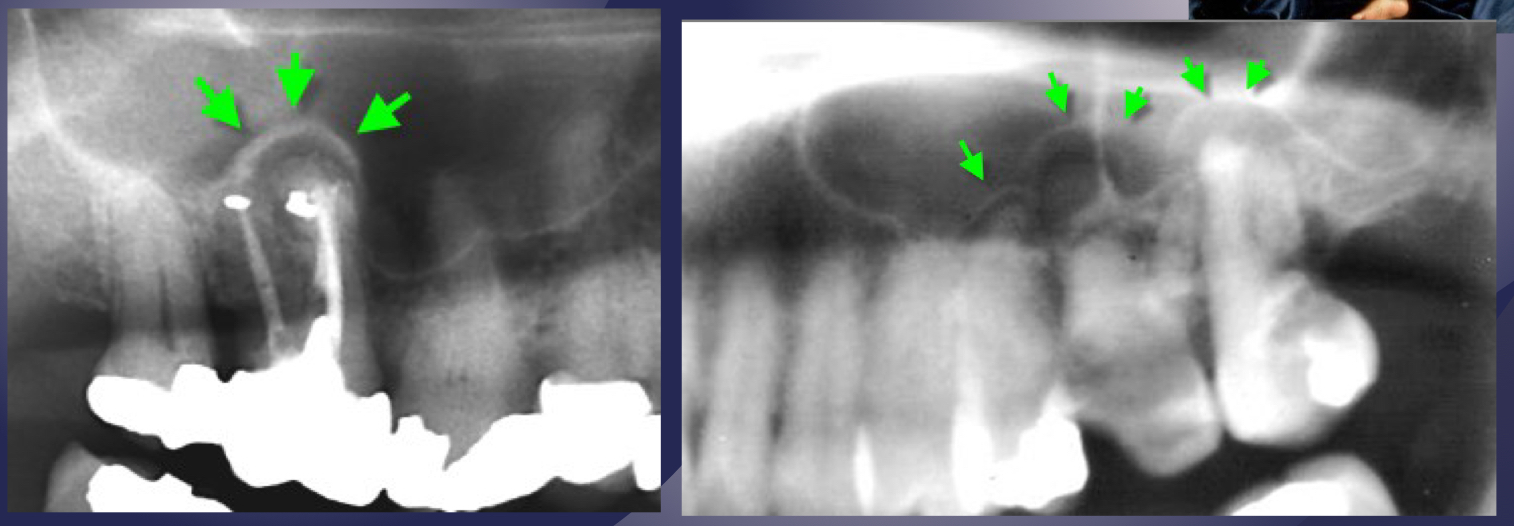

in maxillary M lift floor of max sinus!

elevation/displacement of floor f maxillary sinus

periosteal bone formation in floor of maxillary sinus

periostitis and mucositisÂ

mucosal thickeningÂ